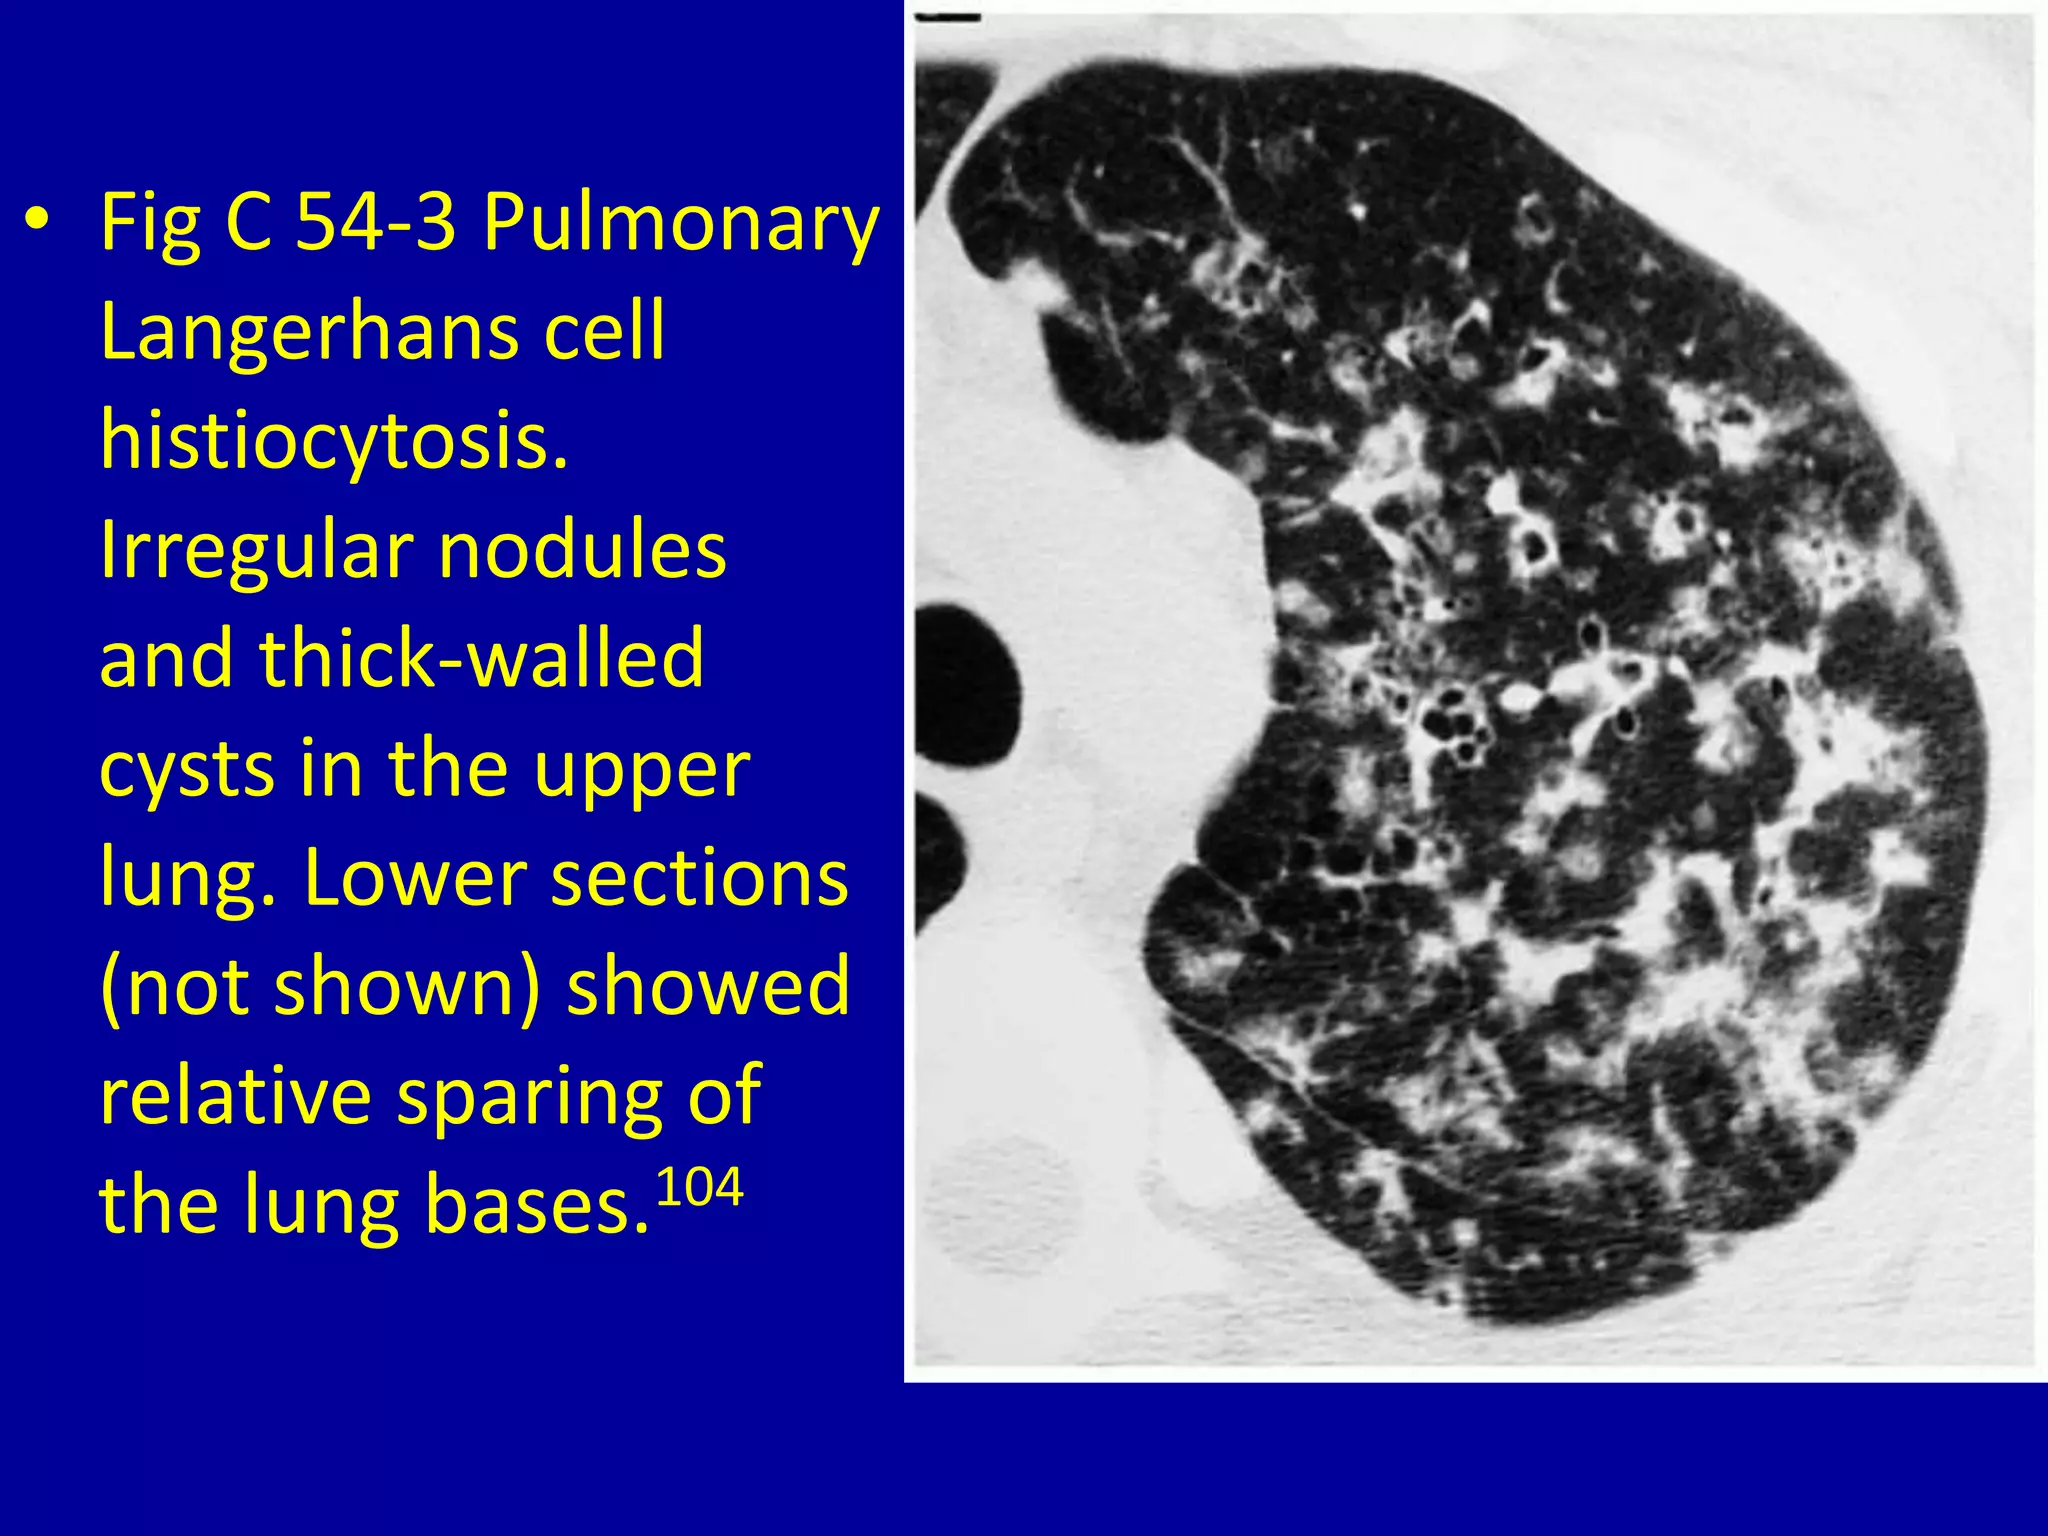

This document discusses various pulmonary diseases that predominantly affect the upper zones of the lungs. It includes 10 figures showing CT scan findings of different conditions like postprimary tuberculosis, sarcoidosis, pulmonary Langerhans cell histiocytosis, silicosis, centrilobular emphysema, chronic eosinophilic pneumonia, cystic fibrosis, allergic bronchopulmonary aspergillosis, neurogenic pulmonary edema, and ankylosing spondylitis. The images demonstrate lesions, nodules, consolidations, cysts, and other abnormalities that are largely limited to the upper lobes and regions of the lungs.